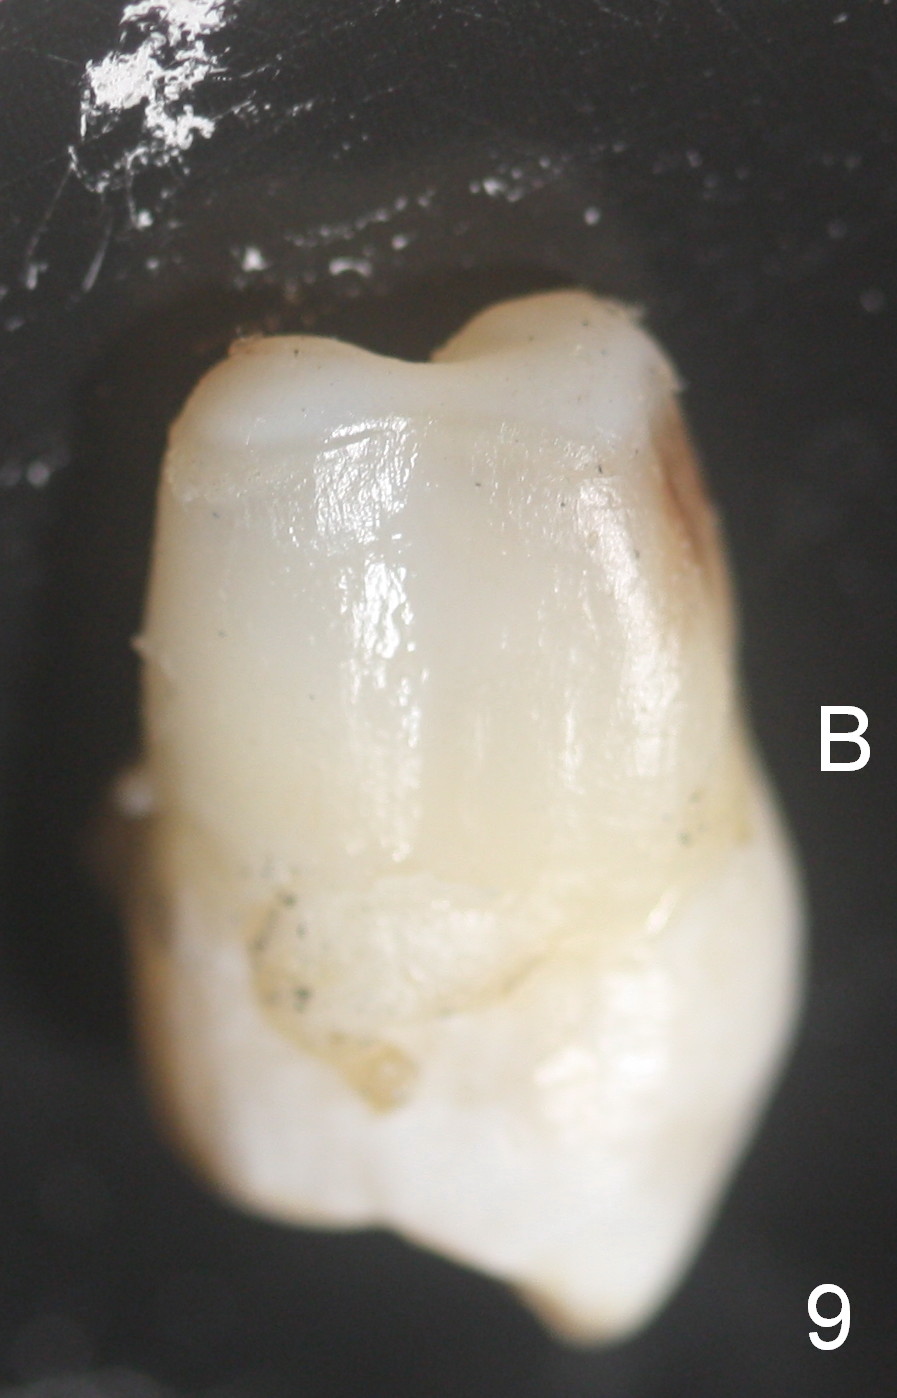

For upper and lower right crowding, series extraction is planned. First the tooth B is extracted. Within 1.5 months, the tooth #5 is erupting (Fig.4 (9 years 4 months old)). It will be extracted once it is fully erupted.

One month later, the tooth #5 erupts more (Fig.5,6) and is extracted (Fig.8-10). The tooth S is to be extracted to make room for #27 and 28 eruption (Fig.7).